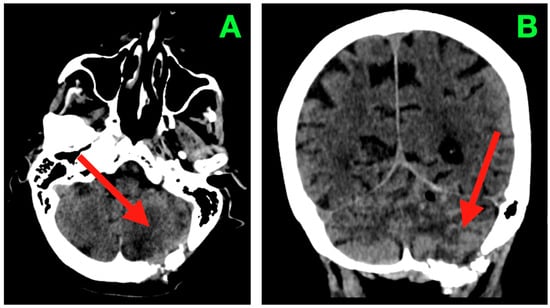

Magnetic resonance imaging of the brain (Figure 1) was performed using multiplanar acquisitions in T1-weighted, T2-weighted, fluid-attenuated inversion recovery (FLAIR), and susceptibility-weighted sequences. The study revealed a single space-occupying lesion in the left cerebellar hemisphere with morphology and displacement that mirrored the patient’s neurological examination.

Figure 1. Pre-operative magnetic resonance imaging of the brain demonstrating a solitary left cerebellar hemisphere mass with associated vasogenic edema and mass effect on adjacent infratentorial structures. The lesion is approximately 40 mm in diameter as measured by multi-planar MRI in each axis (AP ≈ 40 mm; ML ≈ 40 mm; CC ≈ 40 mm) and thus has a calculated volume of about 30–35 cm3 based on the ABC/2 formula. In addition, the upper margin of the lesion is less than 3–4 mm from the tentorial insertion, and the lower margin of the lesion is greater than 8–10 mm from the foramen magnum with preservation of the cisterna magna. The lesion contacts but does not invade the dentate nucleus and displaces the fibers of the middle cerebellar peduncle. (A) Coronal T1-weighted image showing an iso- to mildly hypointense lesion (arrow) expanding the left cerebellar hemisphere, with the superior margin following the tentorial surface, medial indentation of the superior vermis, and rightward displacement of the fourth ventricle without overt hydrocephalus. (B) Coronal T2-weighted image depicting a hyperintense lesion (arrow) with internal signal heterogeneity and surrounding vasogenic edema radiating toward the middle cerebellar peduncle; the edema distribution involves the trajectory of dentatothalamic and corticopontocerebellar pathways. (C) Coronal FLAIR sequence in which suppression of CSF signal enhances delineation of the edema margins (arrow), showing medial extension into the paravermian white matter, narrowing of the perivermian cistern, and gentle anterior displacement of the dorsal pons. (D) Sagittal FLAIR view demonstrating the anteroposterior extent of the lesion (arrow) from the region anterior to the posterior medullary velum to the convexity of the cerebellar hemisphere; the superior margin lies in close apposition to the tentorial leaflet, while the inferior border remains above the foramen magnum, preserving the cisterna magna. (E) Axial susceptibility-weighted image revealing multiple punctate hypointense foci within the lesion (arrow), suggestive of intralesional blood products, with a sharply demarcated border from surrounding edema and no evidence of additional posterior fossa lesions.

On the coronal T1-weighted imaging (Figure 1A), the lesion was associated with iso- to mildly hypointense signal compared with neighboring cerebellar cortex, with a curved convex lateral border extending the hemispheric contour. The superior border followed the tentorial surface with small intervening CSF, and the medial contour extended into the superior vermis, where it caused a subtle flattening of the midline contour. Its inferior pole extended to slightly above the level of the cerebellar tonsil and had a small amount of CSF within the cisterna magna. The mass effect was generating medial displacement of the fourth ventricle to the right and decreasing the caliber of the left lateral recess. The mass effect contended for some space to partially narrow the foramen of Luschka without cranial dilation of the fourth ventricle, as is typically observed with significant upstream ventricular dilation. Aside from the lateral recess being displaced midway, there was a small rotation of the ventricular axis, a characteristic that is clinically relevant to intra-operative navigation in this confined area of the posterior fossa. On the coronal T2-weighted image (Figure 1B), the lesion was seen as significantly hyperintense with internal signal heterogeneity, suggesting variability in tissue components as well as localized fluid. There was a large T2 signal in the surrounding cerebellar white matter which extended medially into the paravermian white matter and anteriorly toward the middle cerebellar peduncles, which suggested there was diffuse vasogenic edema. The edema assumed a pathway that probably followed the dentatothalamic efferents traversing the superior cerebellar peduncle and the afferent corticopontocerebellar fibers passing through the middle cerebellar peduncle, both of which are functionally important tracts. The superior margin of the lesion created a subtle elevation and flattening of the tentorial insertion line on the left, indicating transmitted mass effects into the supracerebellar compartment. The coronal FLAIR sequence (Figure 1C) provided excellent definition to the margins of the lesion and edema, as the signal from CSF was suppressed. The hyperintense halo of edema extended from the lateral hemisphere inwards to the paravermian area, narrowing the perivermian cistern and partially effacing the posterior recesses under the fourth ventricle. The dorsal surface of the pons appeared to be slightly flattened and displaced anteriorly, but the aqueductal inlet still appeared to be patent. The angular formation of edema, which was directed medially and anteromedially, suggested that the primary vector of pressure from the lesion was pressing up against the midline vermian structures and the brainstem–cerebellar interface rather than being directed inferiorly towards the foramen magnum. Both the coronal and sagittal FLAIR (Figure 1D) sequences provide a complete anteroposterior view of the lesion spanning anteriorly near the posterior medullary velum to the convex posterior cortical surface of the cerebellar hemisphere. The upper margin was very slightly apposed to the lower surface of the tentorial leaflet in a position that was physiologically compressed such that there was a thin plane of CSF interfacing the midbrain and the tentorial tentorium layer, limiting the potential upward cerebellar ‘relaxation’ during the exposure. The inferior interface was likely approximately 6 mm from the cranial foramen magnum with some preservation of the cisterna magna and its ancillary role in controlling CSF release at the initial opening of the dura. The dorsal displacement of the brainstem was exaggerated in this imaging plane. Note that there was also gentle anterior bowing of the superior medullary velum. The axial susceptibility-weighted image (Figure 1E) showed multiple punctate hypointense foci in the tumor, likely representing distant intralesional blood product deposition, either hemosiderin or deoxyhemoglobin, and presenting some evidence of a lesion with vascular channels supporting microhemorrhage. The sharp interface noted between the lesion core and surrounding hyperintense edema, and the absence of satellite nodules or evidence of multifocal disease within the posterior fossa, again suggested a well-defined lesion. While the cranially located vein of cerebellopontine fissure and the adjacent cortical veins from the hemispheric were open, the proximity of the adjacent draining veins highlighted the need to protect venous drainage during tumor exposure and resection.

In sum, the imaging described a tumor that was well-circumscribed and expansile in the left neocerebellar hemisphere where there was a mass effect toward the vermis medially, to the brainstem anteriorly, and toward the tentatorial insertion anteriorly. However, based on the immediate degree and direction of displacement with imaging and proximity to the fourth ventricle and outlets, even the potential for obstructive hydrocephalus remained precarious, such that even small further lesion enlargement or intratumoral hemorrhage could lead to acute obstruction. The proximity of the tumor to the middle cerebellar peduncle and dentate nucleus illustrated that operative dissection would need to take account of both the afferent and efferent connections of the cerebellum and the deep cerebellar nuclear microarchitecture identified within the tumor. The vascular signature demonstrated in the SWI suggested that if intratumoral decompression were attempted, then intratumoral decomposition would need to be undertaken with stepwise hemostasis with early control of arterial feeders and selective attention to preserve the integrity of venous drainage. As this pre-operative imaging established the anatomical and radiological relationships, it may have ultimately guided and directed the surgical approach, including working angles and dural opening, and consideration of the later order of tumor debulking/capsule dissection.